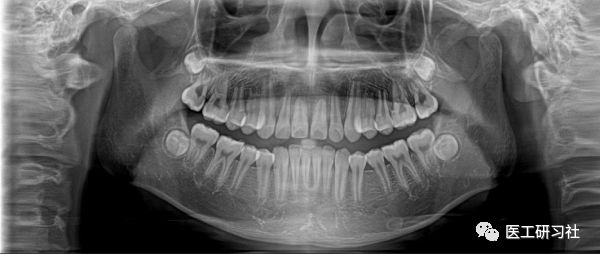

全景机基于体层摄影原理设计而成,其成像逻辑与乳腺DBT非常相似。全景摄影时,根据口腔颌面部的解剖特点,X 线球管围绕人体头部选择约120°,从一侧颞下颌关节到另一侧颞下颌关节,最后一次性获得全口牙齿的2D图像,使颌骨及全口牙体层摄影在一幅图片上呈现左右展开的平面图。

全景图像(来自互联网)

全景机具有观察全面、操作简便、儿童及老弱患者容易接受的优点。然而,全景机的缺点也非常明显:

1)相较牙片机,全景成像中牙齿内部的清晰度和细节明显要略逊一筹;

2)由于是曲线体层成像,其图像有比较严重的畸变失真,同样也不可避免的具有影像重叠。

因此,全景机主要用于观察所有牙齿的形态、位置及颌骨内情况,为牙齿正畸矫正、牙齿修复提供图像依据,不太适合用于对牙齿结构成像清晰度要求非常高的领域。